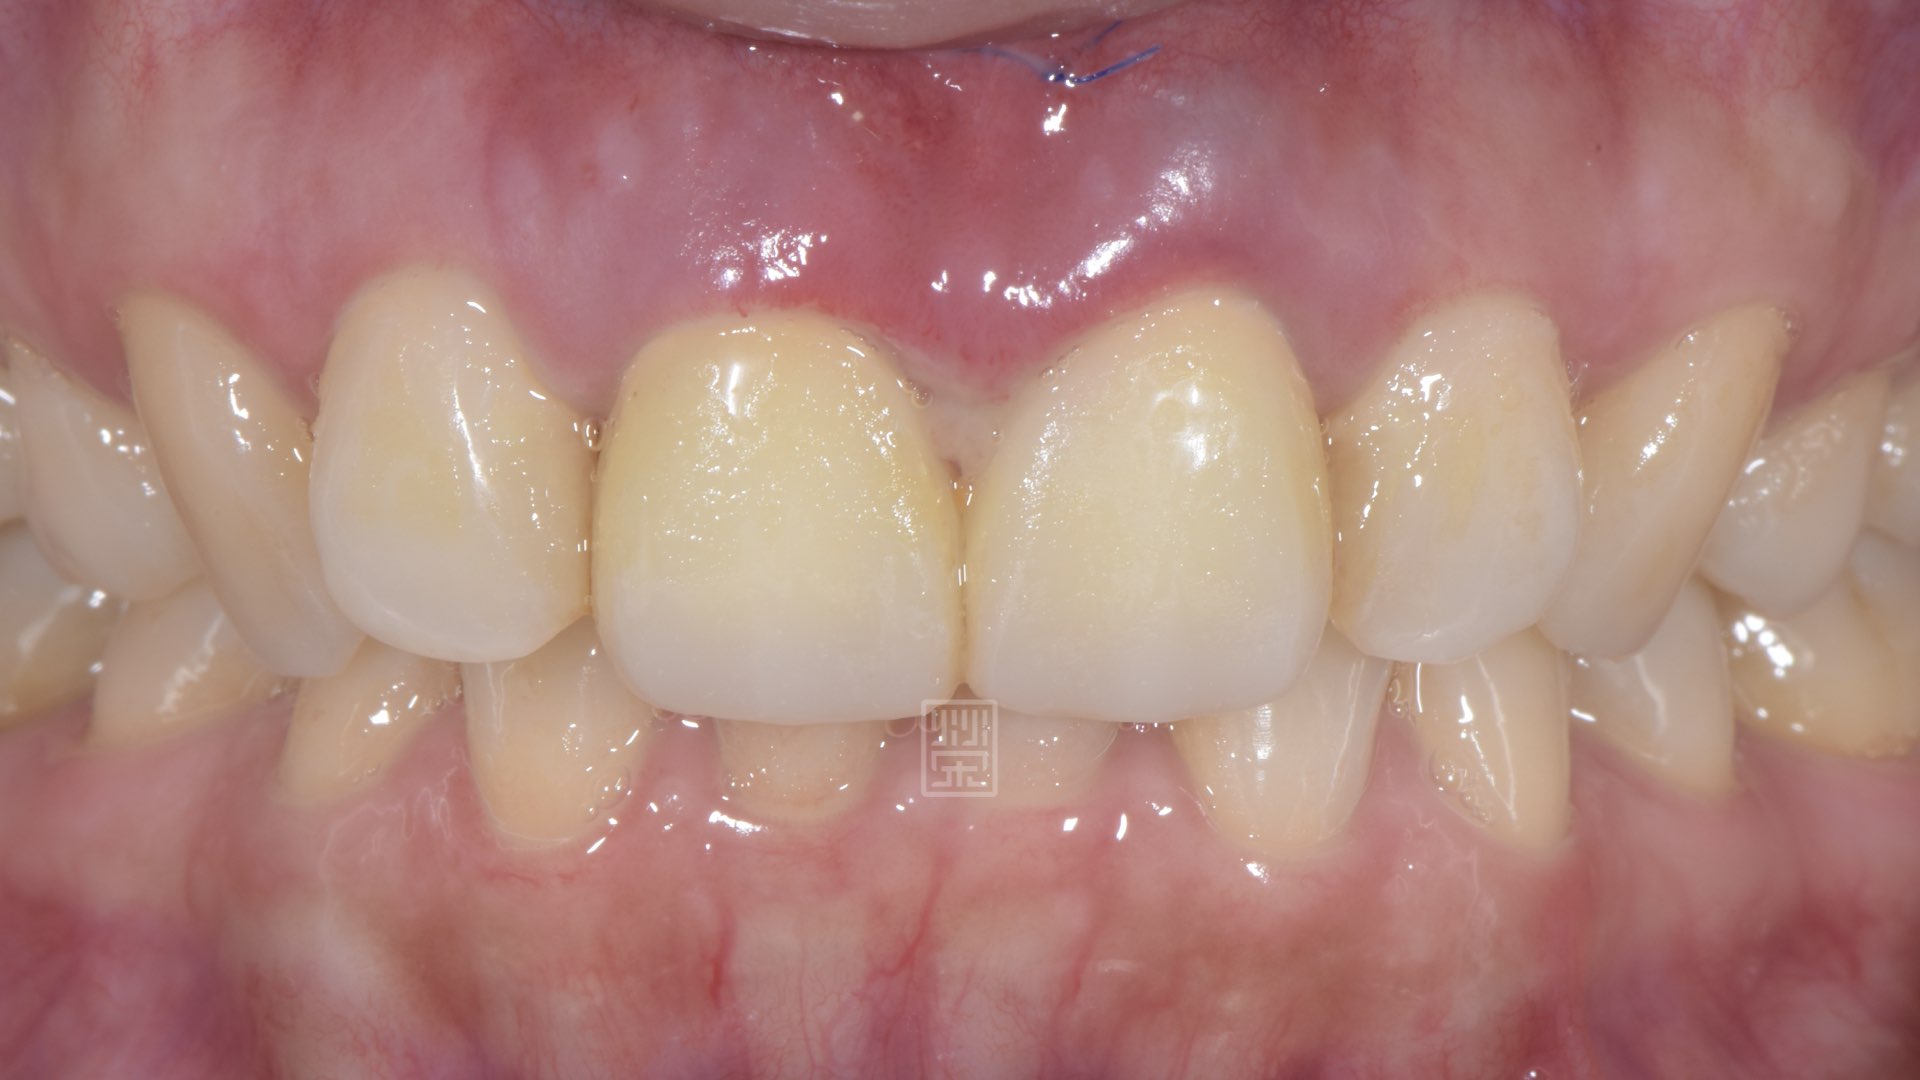

手術後癒合穩定

兩週後傷口修復